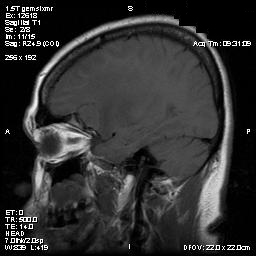

Clinical information The patient was a 54 year-old woman with a history of diabetes. She developed vomiting and frontal headache for two days. As per the descriptions of her family members, she had a few episodes of starring into the left and was unresponsive. The patient described that she could remember all these episodes clearly. On physical examination, the patient was well oriented and alert. There was no weakness in the extremities, ophthalmoplegia, diplopia, reduced visual acuity or facial weakness. An MRI and a CT scan were performed and yielded the following representative images. A surgery was performed. Representative photographs of the specimen are illustrated below.

Com405-1-Imag-1.gif (48010 bytes) Com405-1-Imag-2.gif (49140 bytes) Com405-1-Imag-3.gif (37591 bytes) Com405-1-Imag-4.gif (44330 bytes) Com405-1-Imag-6.gif (109828 bytes)

A. B. C. D. E.

T1-weighed MR images demonstrate an extraaxial, dural based mass involving the right supraorbital region  (Panel A and B). The mass shows homogeneous enhancement  (Panel C). CT scan demonstrates as well as rim calcification (Panel E). On T2-weighed imagers, significant vasogenic edema is demonstrated despite the small size of the lesion and the extraaxial location (Panel D).